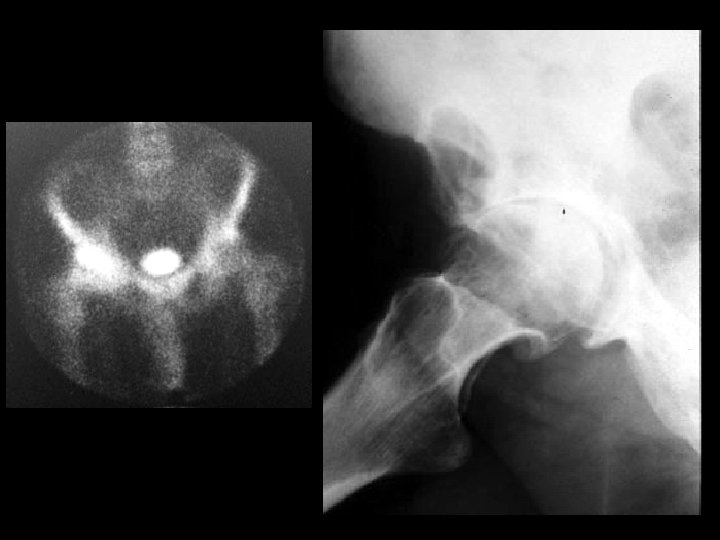

Neurofibromatosis Type I • Findings: – Enlargement of multiple neural foramina and scalloping of the posterior vertebral bodies • ddx: – NONE! – This is an aunt Minnie!

Severe OA & Geode • Findings: – severe osteoarthritis of the right hip – lytic lesion in the adjacent superior acetabulum – hot on bone scan • ddx: – fibrous dysplasia – ABC – infection – erosion